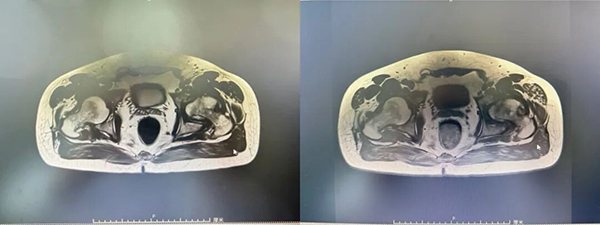

术前MRI:

来到生态城医院骨科后,检查结果揭开了真相:左侧股骨头缺血性坏死(ARCO分期Ⅳ期)——股骨头已经塌陷变形,保守治疗已无能为力。